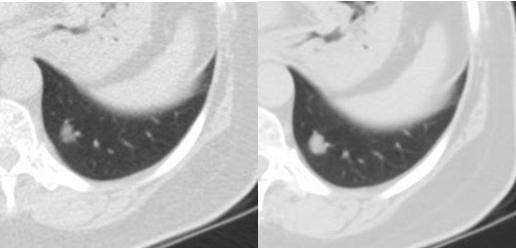

(左肺下葉小結(jié)節(jié),左圖為低劑量,右圖為常規(guī)劑量)